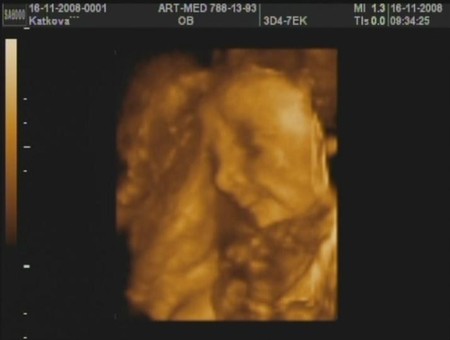

Беременность и РОДЫ16 ноября были на 3Д-узи.. Ездили в арт-мед на Дмитровке в воскрессенье!!!! В 9 Утра!!!

Показали нам нашего масика и даже записали на диск))) С мужем уже его заездили!!!))) смотрим каждый вечер перед сном, никак не можем налюбоваться)))

Подтвердили аж трехмерно, что у нас пацан и сомнений тут никах не может быть!!! Вот.. полубуйтеся...

Правда понятно, что ничего не понятно на этих фотографиях... (всмысле на кого похож будет, но основные черты уже проглядываются))))